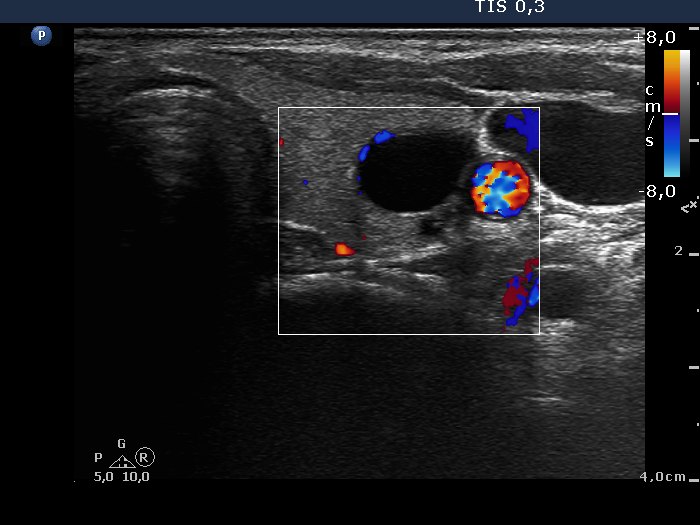

100 consecutive cases of papillary cancer - case 001 (ultrasonographic picture 6)

Left lobe, transverse view, color Doppler mode. The vascularization is not specific.